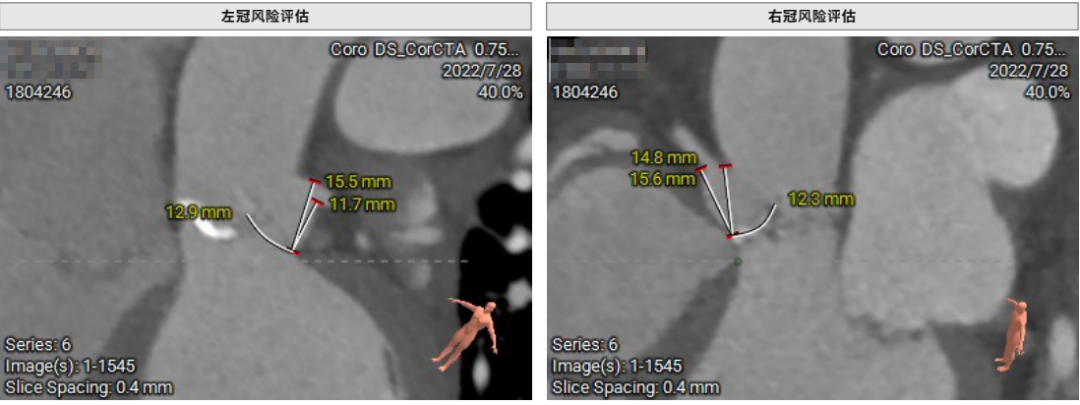

患者64岁男性,Type 0 型二叶瓣、横位心。主动脉瓣中度狭窄,重度反流,瓣环周长92.0mm,平均径29.0mm。LVOT周长98.7mm,升主扩张,窦部结构极限,锚定能力极限。入路两侧血管轻度迂曲,分叉高度可,两侧血管内径均>8mm。

患者左、右冠高度,瓣叶长度,窦宽相对瓣膜均尚可,冠脉风险低。但由于患者重度AR,可能因植入深度和选择大型号瓣膜,带来较高的传导阻滞风险。其次,患者升主扩张,存在破裂风险。最后,患者是横位心,瓣环及流出道结构大,术中瓣膜释放的位置达到了极限,瓣膜释放后可能会发生位移,有瓣中瓣风险。

首先,最重要的是观察瓣环结构,理论上如果瓣环周长超过85mm,尽量就不做;第二,看流出道情况,最好是直筒状的,瓣环和瓣下4mm的直径比值,理论上不能超过1:1.1,如果超过1.1以上就变成喇叭状,也不建议做;第三,避免存在升主动脉显著扩张,如果扩张明显,无法提供有效的锚定。总体来说,最主要的一定是瓣环直径,瓣叶有没有增厚,瓣叶有没有钙化,瓣环能否有效固定住植入的瓣膜。瓣环的固定和锚定条件,是反流患者能否进行TAVR的决定因素。